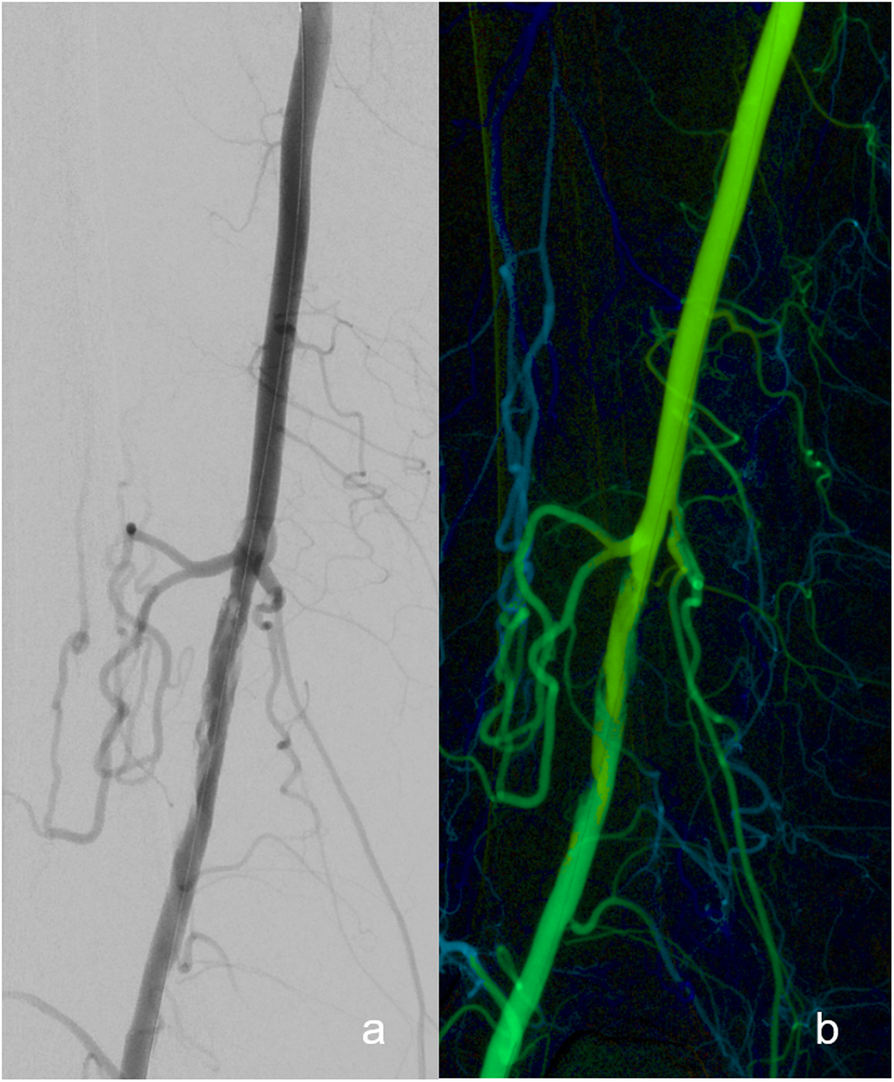

Fig. 2

a Conventional digital subtraction angiography (DSA) with corresponding color-coded DSA image of a patient after percutaneous transluminal angioplasty (PTA) of the SFA displays a dissection. b Correlating color-coded DSA image revealed no relevant limitation of blood flow